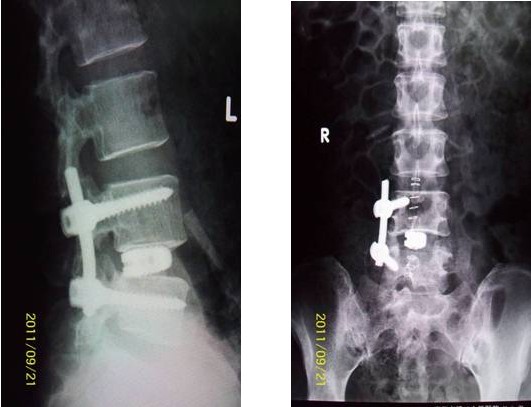

病例匯報2老年女性患者,因“反復(fù)腰腿痛10年、加重伴左下肢麻痛3年”之主訴入院,術(shù)前間斷性跛行,左下肢肌力3+級,淺感覺減退。術(shù)后腰腿疼緩解,肌力及感覺恢復(fù)正常。(1、圖2)

術(shù)后腰椎X線提示單側(cè)釘棒系統(tǒng)固定穩(wěn)妥,椎間隙高度恢復(fù)正常,融合良好。(圖2